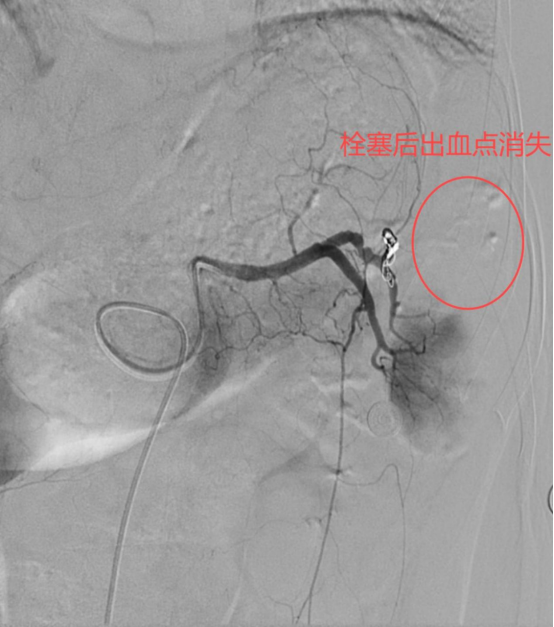

▶ 弹簧圈

这像“小塞子”,医生把“塞子”送到出血的地方,把出血的“洞”堵住,以此来止血。

不管是哪种神器,堵住的只是一条出血的分支,其它血管分支还在正常运行,因此脾脏不会“死掉”。

通过血管造影定位破裂血管,用栓塞材料封堵出血点,避免开腹手术。